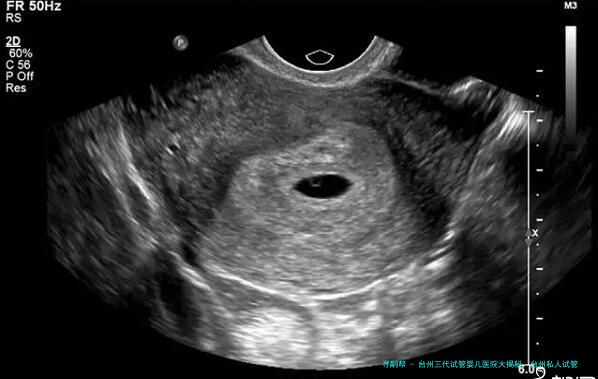

试管婴儿技术也需要到了很大的发展。在台州私人试管医院内,选用的是最先进的三代试管婴儿技术。这种技术相比较于传统的2代试管婴儿技术更加准确和高成效。它通过对卵子和精子进行试管受孕,并在培养皿中培育出胚胎,然后再将胚胎移植到母亲体内,从而达到怀孕生育的目的。